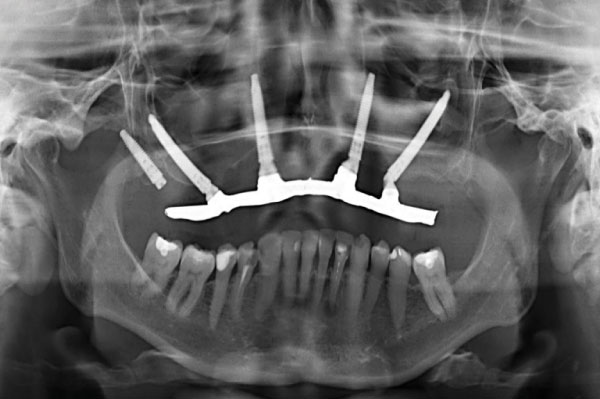

Types of Dental Implants: Which One is Best?

Modern dentistry has developed 3 types of dental implants, best known for their long endurance, high success rate and overall reliability.

Depending on your circumstances, one type might be better than the other. The decision is yours, but we advise you to pay careful attention to your dentist’s recommendations: